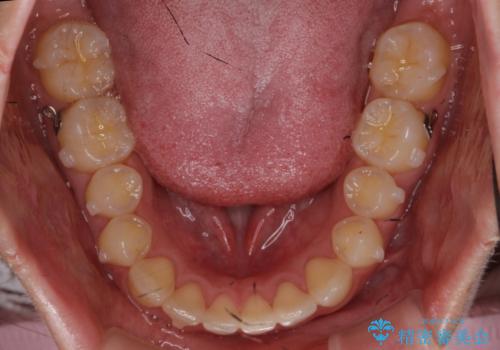

下の前歯が1本短い インビザラインと部分矯正の組み合わせ

- 前歯のガタつきと、下の前歯が一本短いことを主訴に来院。

インビザラインのマウスピースではめる装置で歯を引っ張り出すことは難しいと説明し、下の前歯だけワイヤー部分矯正を行ってからインビザライン矯正で仕上げをしました。

周りには気にしなくていいのではと言われていたが、やってよかったと非常に満足されていました。

難しい部分を短期間ワイヤー矯正を行ってからのインビザラインは、全体治療が短くなるだけでなく、仕上がりもよくなるのでオススメです。